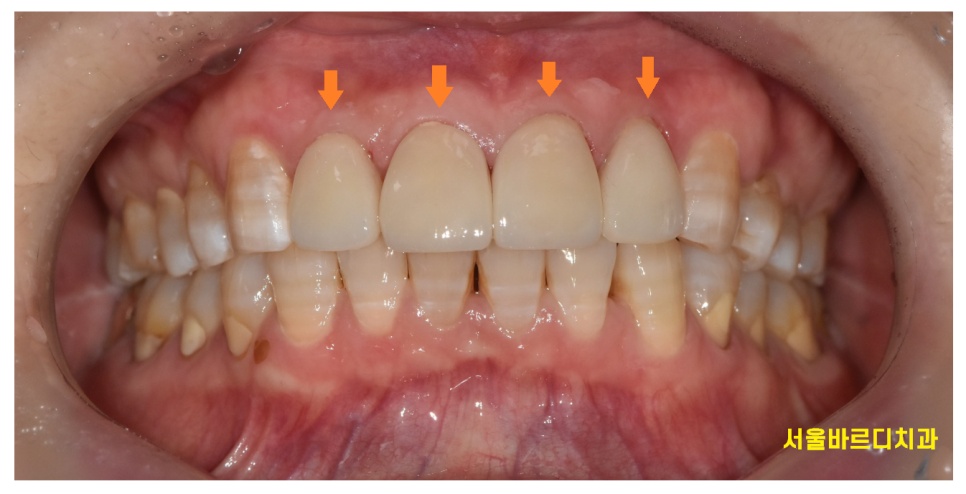

250228 라미네이트 부착 후 입니다. 공간이 메꿔지니 훨씬 자연스럽죠~???

부착 후 입 모습이에요.

앞니 사이 벌어짐 공간을 메꿔드리다보니

치열도 정리된 느낌이고

심미적으로도 변화가 커서

환자분이 예쁘다고 굉장히 만족해하셨어요!!

250307

치아 사이 벌어짐 라미네이트로

환자분의 컴플렉스를 극복해드렸는데요!

기존 내 치아 삭제량도 크지 않으면서

라미네이트를 부착한 모습

치아 크기가 커지지도 않고

자연스럽죠~??